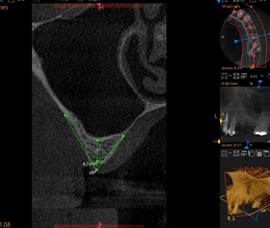

Pacjentka lat 72, od kilkudziesięciu lat chorująca na cukrzyce I typu, obecnie od 10 lat na pompie insulinowej. Profesor medycyny, siostrzenica pacjentki prowadzi swoją ciocię diabetologicznie, pacjentka świadoma zagrożeń przy zabiegach regeneracji kości i implantacji w takim ogólnym stanie zdrowia. Po rekonstrukcji tkanek miękkich i kości osadzono dwa implanty o średnicy 5,0 mm. Na zdjęciu śródzabiegowym widać zadowalające wyniki rekonstrukcji tkanki kostnej. Po upływie kilku miesięcy wykonano nadbudowę protetyczną.